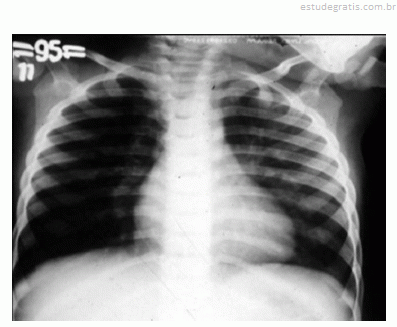

Um lactente de quatro meses de idade cronológica, nascido prematuro de vinte e nove semanas gestacionais, apresentou, durante o inverno, febre, tosse e dificuldade respiratória nos últimos três dias antes de ser levado por sua mãe à emergência pediátrica. A mãe relatou que a criança nunca havia apresentado um episódio semelhante a esse. O calendário vacinal mostrou que a criança recebeu duas doses da vacina antipneumocócica decavalente, porém não recebeu palivizumabe. O exame físico da criança mostrou desidratação, taquipnéia, retração intercostal e sibilos inspiratórios e expiratórios. O resultado do hemograma solicitado pelo médico revelou hematócrito de 40%, concentração de hemoglobina de 13 g/dL, 9.000 leucócitos/mm3, 55% de linfócitos, 34% de neutrófilos, 2% de eosinófilos, 1% de basófilos, 8% de monócitos, 340.000 plaquetas/mm3. O médico solicitou radiografia de tórax da criança, cuja imagem é apresentada na figura.